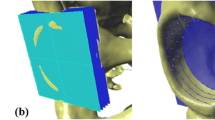

The acetabular axis is defined as the line joining the centers of the circles fitted to the edges determined by the intersection of the lunate surface with the planes parallel to the acetabular-opening plane. The procedure for determining the acetabular axis is as follows: step 1, determining a set of section planes: drawing planes parallel to the acetabular-opening plane, at a distance of 1 mm each, to the top of the acetabulum (Figure 4a); step 2, drawing base curves and points: finding the curve that is the intersection of the lunate surface with reference planes; marking points (at least 30) on each curve (Figure 4b); step 3, fitting circles to the points on curves: using points set on each curve, a circle is fitted to the selected points on each section and its center marked (Figure 4c); step 4, determining the acetabular axis: the axis is established by interpolation the trend line over the centers of the circles (Figure 4c).

Steps to determining the acetabular axis: (a) Generating a set of section planes (parallel to the acetabular-opening plane); (b) finding the curve that is the intersection of section planes with acetabular surface, and subsequent marking of points over the curve; (c) fitting the circles to the intersection points and establishing the acetabular axis by finding an average trend line that joins the centers of the circles.